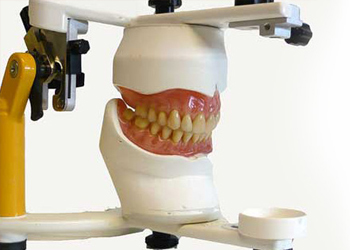

Dentures

BPS Dentures - Bio-functional Prosthetic System

Complete Dentures:Complete dentures are for completely edentulous patients. The entire dentition is reconstructed using artificial teeth and the gingiva- with colored resin.

Complete Dentures:Complete dentures are for completely edentulous patients. The entire dentition is reconstructed using artificial teeth and the gingiva- with colored resin.